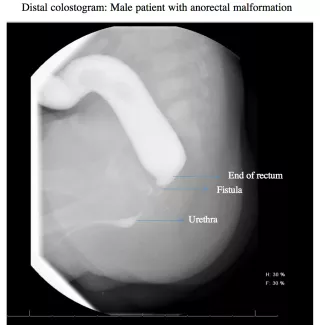

Before the second operation, where an anal opening will be made in the correct location, within the anal sphincter, your child may need to have a radiographic study called a distal colostogram to help prepare for surgery. The study helps to determine the distance from the blind end of the rectum to the skin and if there is a fistula.

If a fistula is found to the urogenital system, it will be closed at the time of the second operation. The stoma will be left intact, and not closed, to allow the new anus to heal. After this operation, the baby can go home to recover.